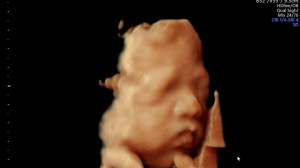

28주 입체초음파

닉네임_박*희_8

2025-09-18